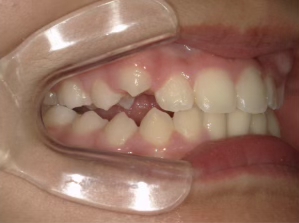

治療中④ 小4:10y1m

左上3が八重歯で萌出中